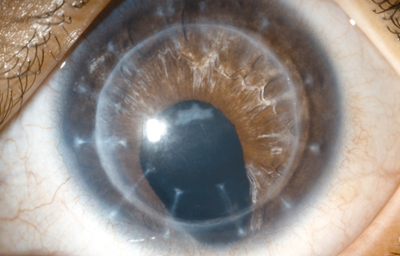

Al examen: Ojo izquierdo con edema difuso de la córnea, bullas epiteliales centrales y cicatriz vertical. Iris con sector inferior, estroma con zonas de “atro a”, Cristalino con opacidad capsular anterior. Tensión ocular digital media; OD Sin alteraciones.- ( Foto No28)

Foto 28 - Foto inicial con edema e iridectomía inferior en sector

Se recomendo Queratoplastia Penetrante de 8.0/ 8.2 mm en el Ojo Izquierdo, que se realizó a los 8 meses del incidente sin complicaciones. Tratamiento postoperatorio con Sherisolona 10mg/dia VO, PredF 3 al dia y Isopto-fenicol 3 al día. Postoperatorio curso sin complicaciones con injerto trasparente, tensión ocular adecuada. A los 6 meses de postoperatorio (190 días) se retiraron suturas bajo anestesia general.- (Foto No29) Refracción: +2.0 (-2.0 x 70o) AVcc Cuenta Dedos

Foto 29 - Foto de la Queratoplastia a los 190 dias

Injerto trasparente, se remitió a Estrabología para tratamiento de ambliopía y se inicio pleóptica pasiva con oclusión del OD

A los 2 años de la picadura: Refracción -0.50 (-1,50 x 60o) AVcc 0.25.- Fijación parafoveal.

Se continuó la Oclusión del OD por varias horas al día.- Se continuaron controles 1 vez al año. Se le recomiendo cirugía de estrabismo pero el paciente no regresó.

Fue examinada por última vez 10 años después de la picadura porque desde hacía 1 mes, disminución de visión y picadas en OI.- Al examen descompensación del injerto con bullas epiteliales: se inició tratamiento y preparación para cambio de Injerto en el Ojo izquierdo que logró realizarse sin complicaciones.- El injerto permaneció transparente por 6 meses cuando consultó por disminución de la visión. Al examen edema total del Injerto: se inició tratamiento pero el paciente NO REGRESO